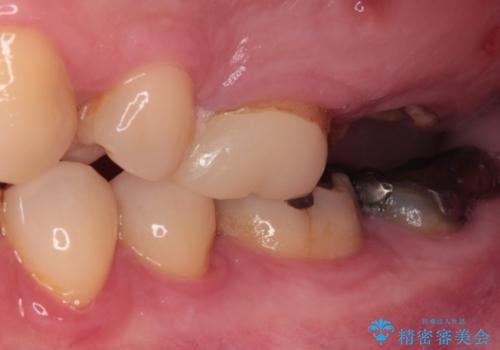

- 奥歯のむし歯と放置したむし歯を気にして来院された患者様です。

奥の歯は抜歯が必要なため、インプラント埋入による補綴治療を行うこととしました。

手前の歯は状態は良くないものの、抜歯するほどではないと判断したため、根管治療後にオールセラミッククラウンにて補綴治療を行うこととしました。